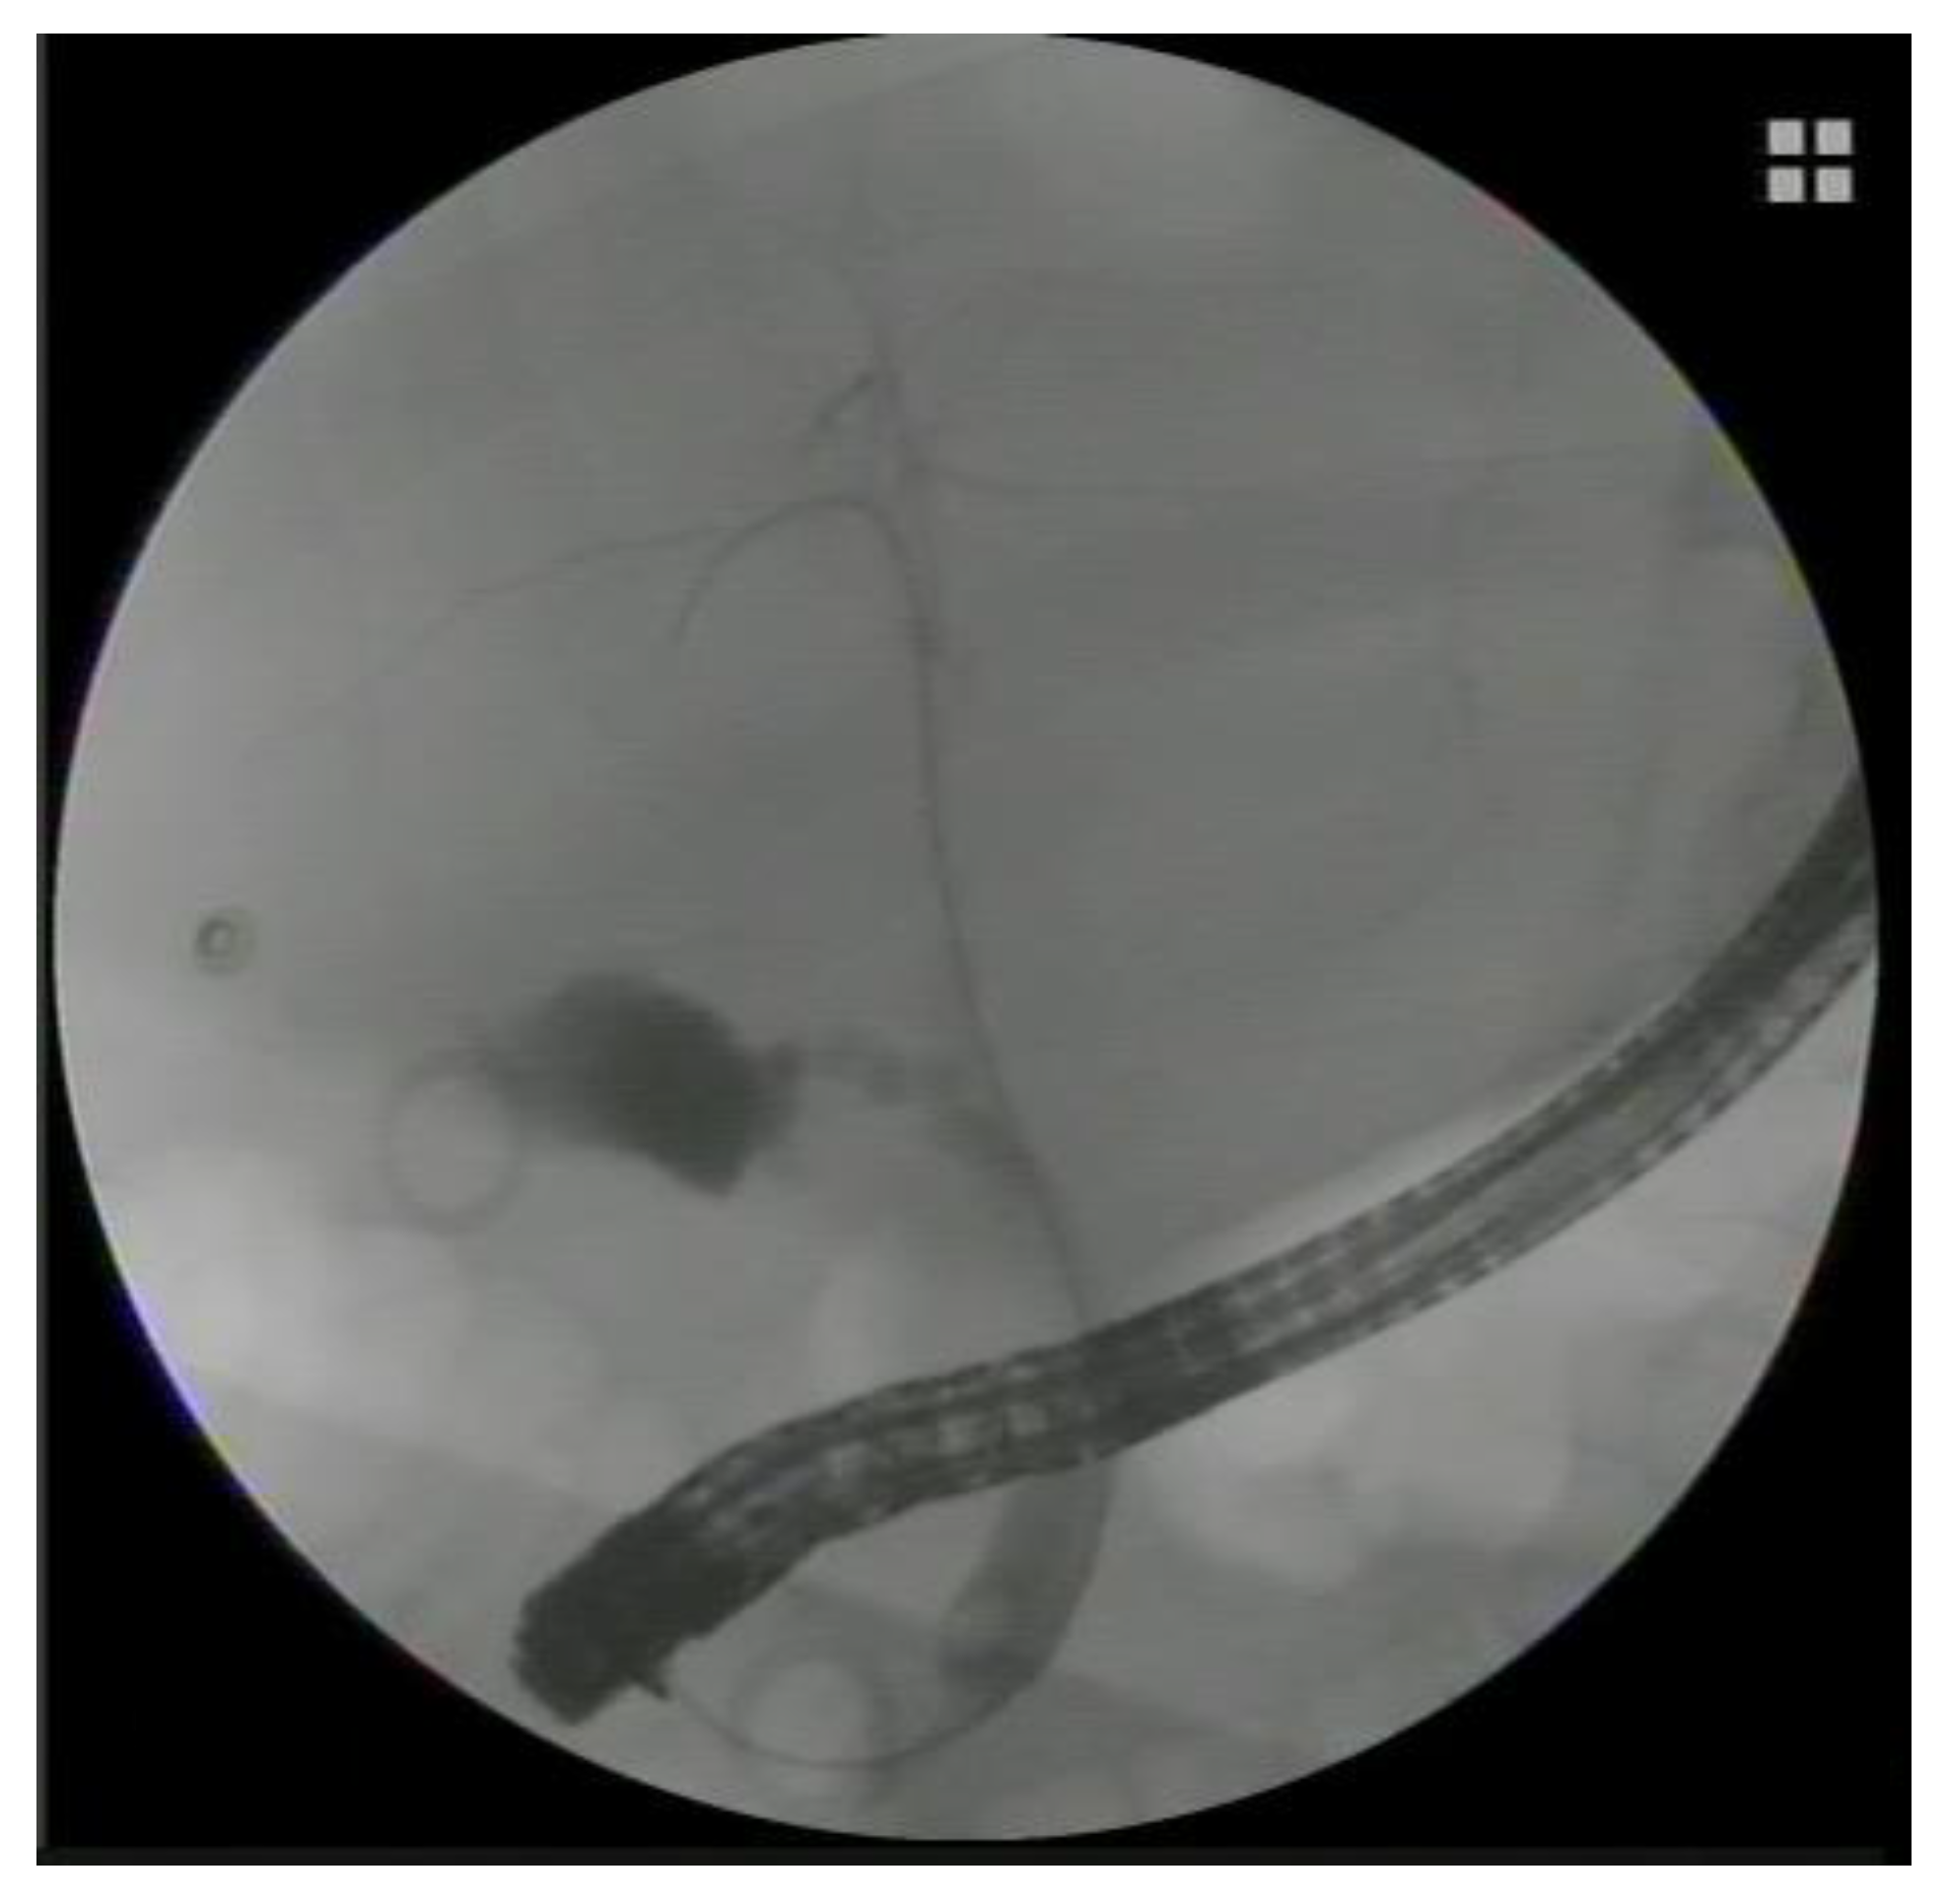

Endoscopic transpapillary stenting. a Endoscopic retrograde Endoscopic Transpapillary Gallbladder Drainage Endoscopic management of acute cholecytitis with transpapillary and transmural drainage of the gall bladder is emerging as a viable alternative. Endoscopic transpapillary gallbladder drainage (etgbd) has been proposed as an alternative to surgery or percutaneous. Endoscopic gallbladder drainage can be considered in patients without evidence of gallbladder perforation or biliary peritonitis. Endoscopic transpapillary gallbladder drainage (etpgbd) is gaining popularity for. Endoscopic Transpapillary Gallbladder Drainage.